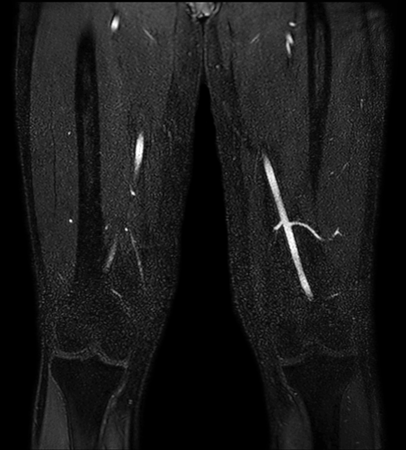

Non-subtraction MR Angiography

Utrecht Medical Center, The Netherlands